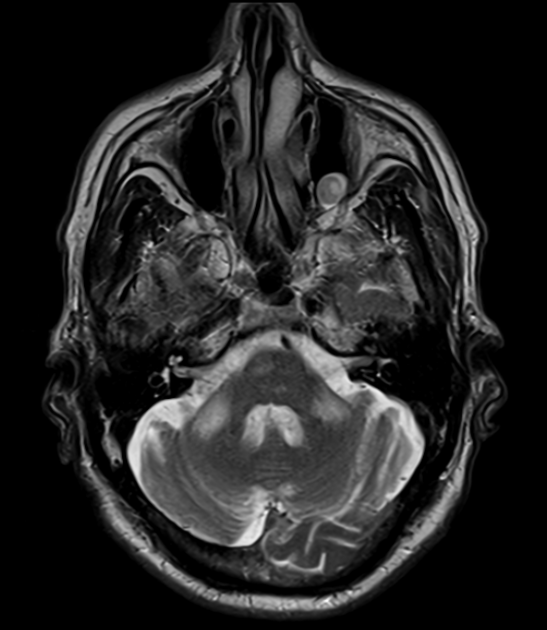

Dandy Walker malformation

agenesis/hypoplasia of cerebellar vermis resulting in cystic enlargement of 4th ventricle

can exist with or without hydrocephalus

can be hypotonic & ataxic